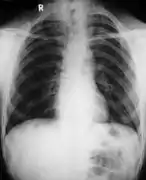

Poor development of the clavicles and a bell-shaped rib cage in a person with CCD